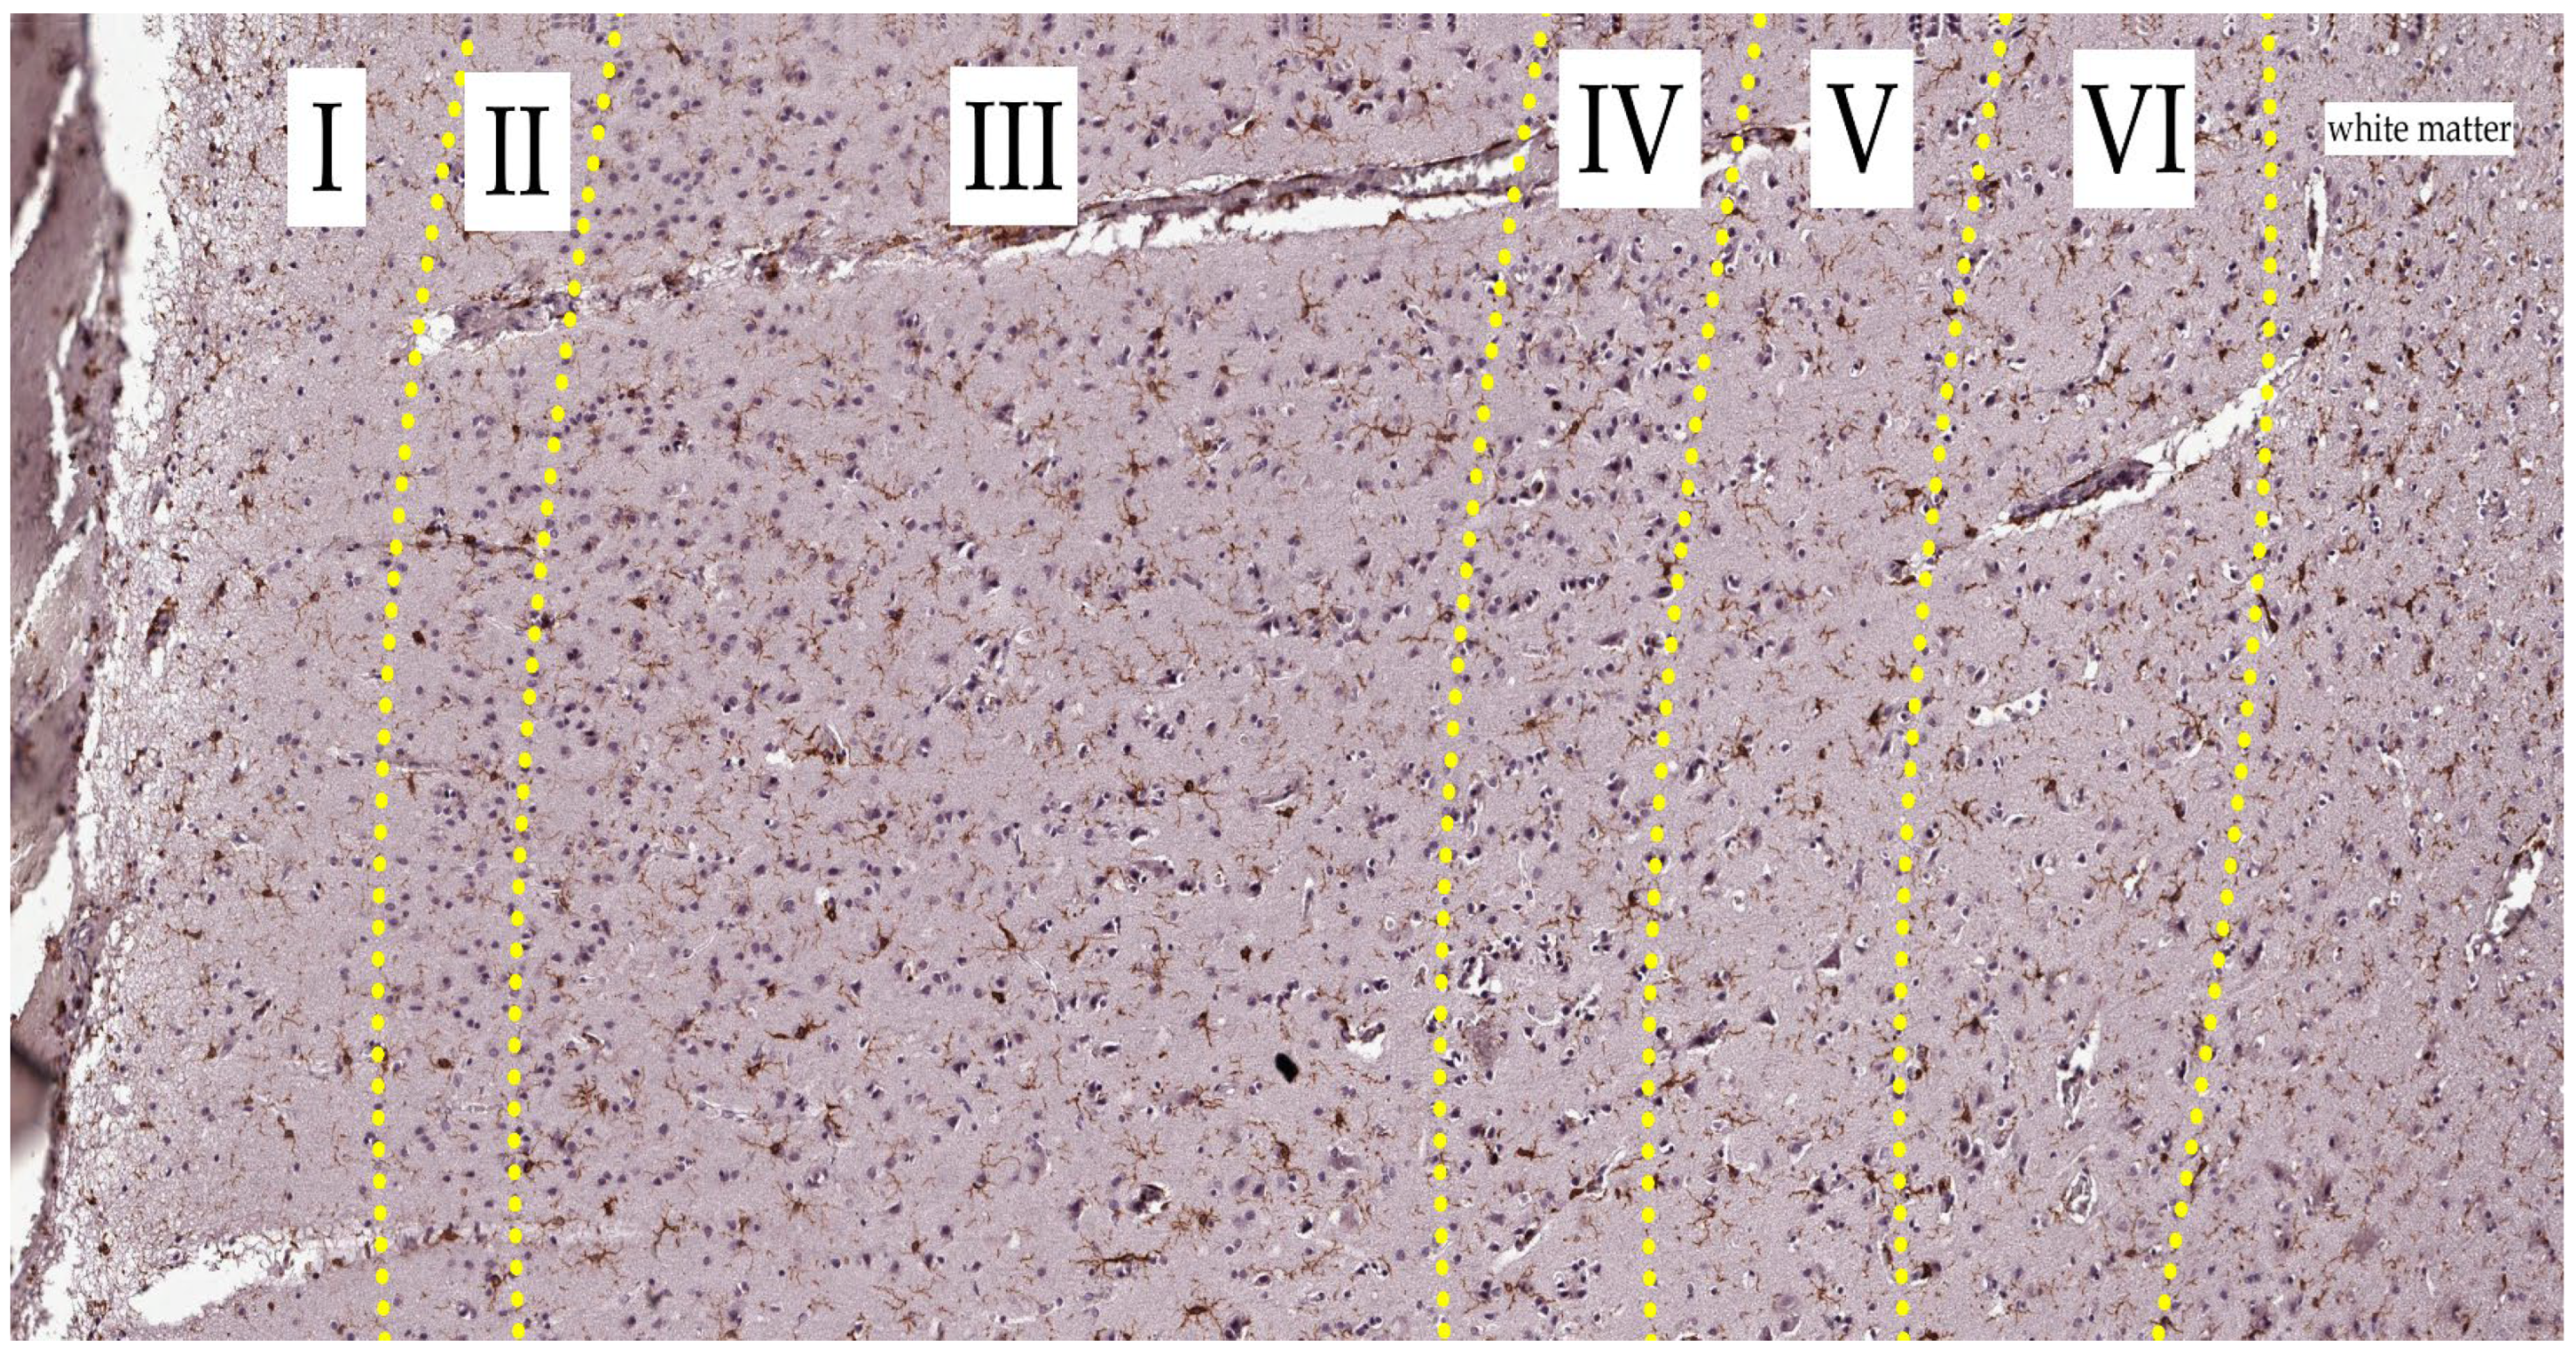

Figure 4.

Cortical region of the control group slide. Iba-1 staining, hematoxylin contrast. Magnification 20x. The yellow dot-line indicates the border between layers. Layers are indicated in Roman numerals.